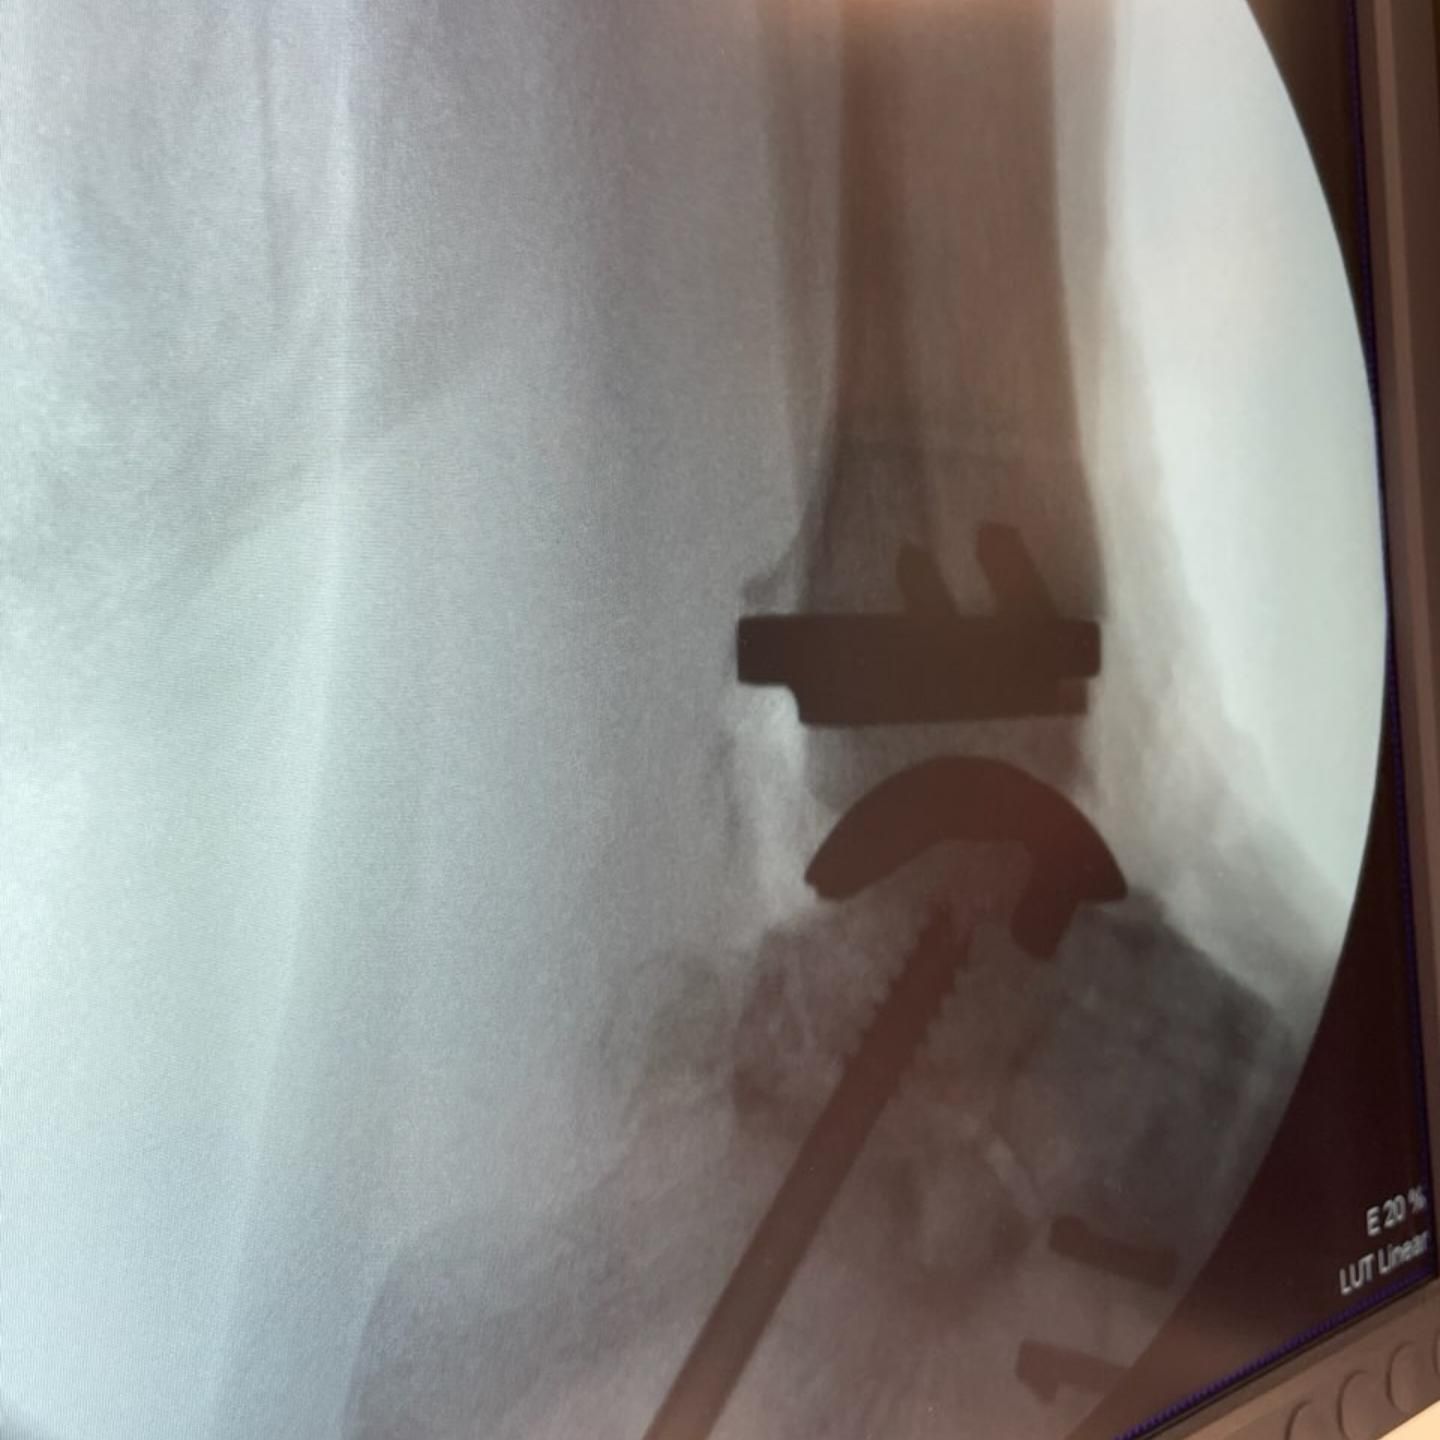

It has been a busy couple of months, but it was a pleasure to fly to Perth to help my friend and colleague Dr Unsworth-Smith with his revision ankle replacement and also to have Dr Ali Vakili observe our technique for ankle replacements.

SPECIAL GUESTS - A DAY IN THEATRE FOR MY NON-SURGICAL SUPPORT TEAM Was great to have "special guests", my own long suffering, hard working secretary @lizzie_hunter01 and podiatrist Helen from @inspire__podiatry who has helped me with my countless post op and foot and ankle patients all these years. They came to theatre to get a glimpse of how surgeries/operating theatres function, so hopefully they can understand, empathise and work better with our patients pre and post op. Helen just wanted to see a total ankle replacement 🤪.